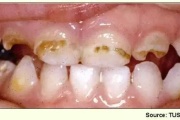

Tetratsükliini liigtarbimise tõttu värvunud hambad

Fluoroos

Fluoroosi

Hammaste defektid